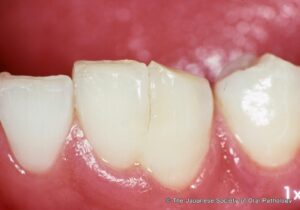

反対に「歯がくっつく」癒合歯とは?

歯が多いとは逆に、

2本の歯がくっついて1本のようになることがあります。

これを癒合歯(ゆごうし)といいます。

癒合歯の特徴

癒合歯では、

- 歯が大きく見える

- 本数が少なく見える

- 歯磨きしにくい

- 虫歯になりやすい ことがあります。

特に乳歯で見られることがあり、下の前歯に多い傾向があります。

保護者の方が

- 「歯の形が大きい」

- 「歯が一本足りない気がする」 と気づくこともあります。